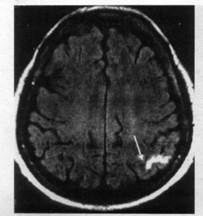

Диагностика ЛИ мозга возможна с учетом особенностей развития и течения заболевания, характера неврологических нарушений, которые возникают на фоне артериальной гипертензии. Однако неврологические синдромы не всегда являются клиническим проявлением ЛИ мозга. Они могут быть обусловлены микрогеморрагиями, другими процессами несосудистого генеза (опухоли, воспалительные процессы, демиелинизация). Поэтому решающее значение для установления диагноза имеет визуализация лакун методами КТ, МРТ и диффузионно взвешенной МРТ (рис. 110). Мелкие лакуны размером до нескольких кубических миллиметров, которые вызывают развитие определенного неврологического дефицита, не всегда можно визуализировать даже с помощью рентгенорадиологических методов исследования. В случае лакунарного статуса методы КТ и МРТ в Т2-режиме позволяют обнаружить специфический феномен лейкоареозис, который характеризуется очаговой и диффузной демиелинизацией белого вещества вокруг желудочков мозга и в полуовальном центре.

МРТ головного мозга через 60 ч от начала инсульта (Т2-взвешенное изображение, аксиальная плоскость, срез на уровне глубоких отделов полушарий большого мозга): гиперинтенсивный яркий очаг (показан стрелкой) свидетельствует о лакунарном инфаркте в таламусе слева (клинически чисто сенсорный инфаркт)